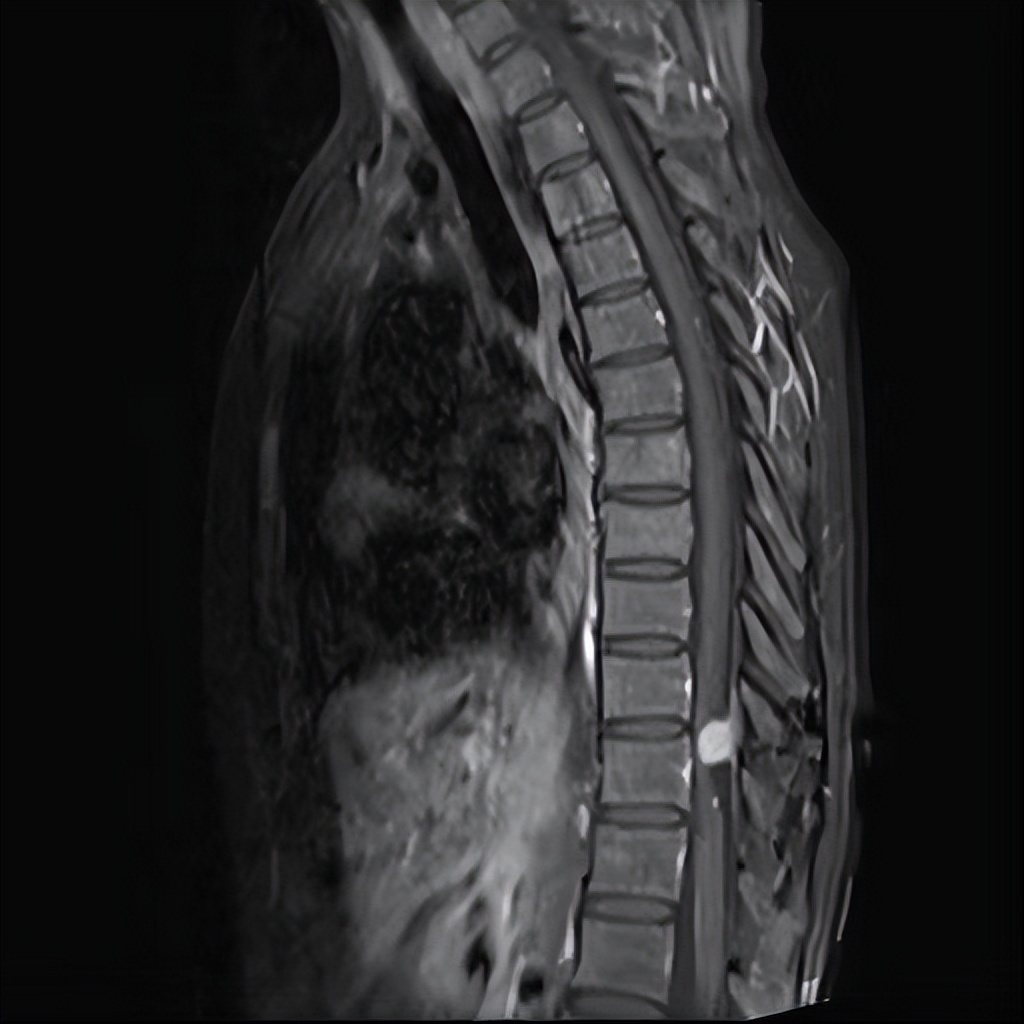

入院后,主管医生何吉洪经过询问病史及仔细查体定位定性考虑是胸椎脊髓疾患,便完善了胸椎核磁共振等检查,检查发现胸椎管内存在肿瘤占位性病变,脊髓受压并变性,诊断为“胸椎管内肿瘤”。

术前MRI